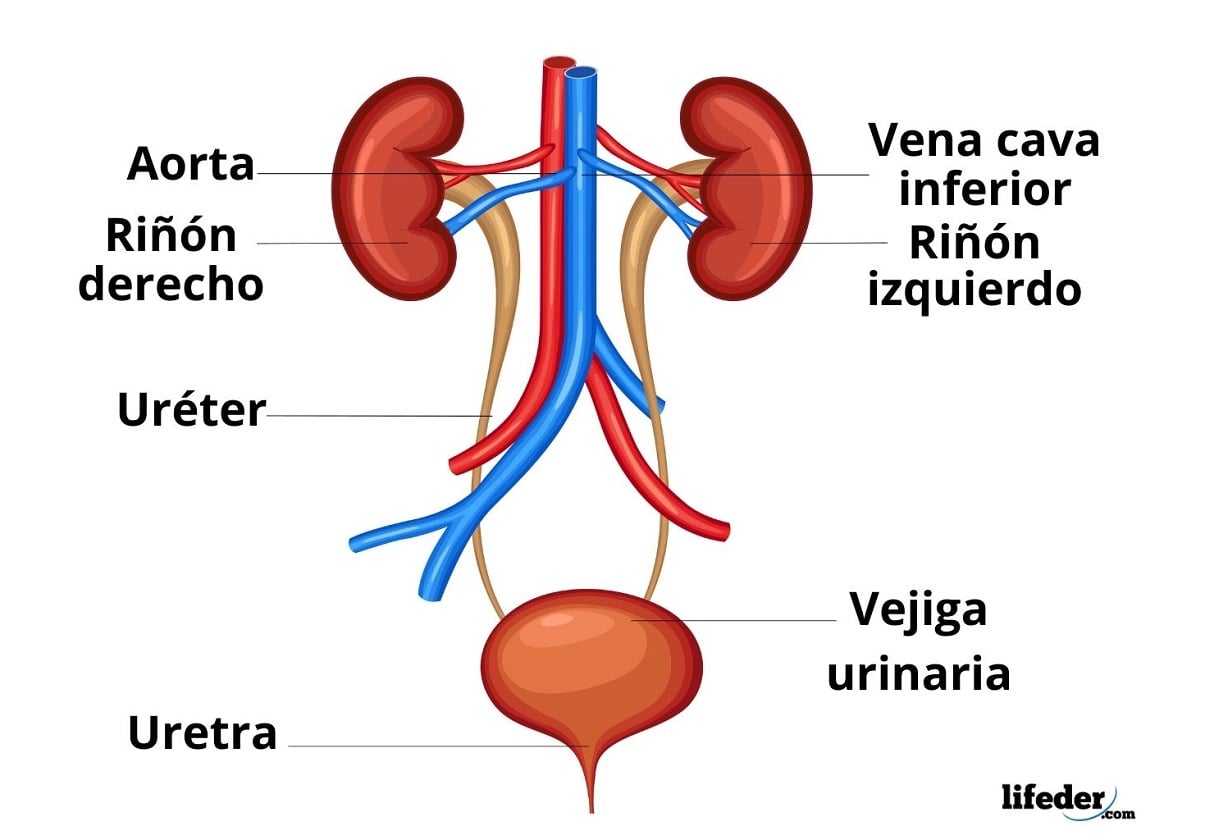

Anatomía humana

Es la ciencia que estudia las estructuras macroscópicas del cuerpo humano. Estudia las estructuras del cuerpo humano por sistemas, como son, el sistema esquelético, el nervioso, el vascular, etc.